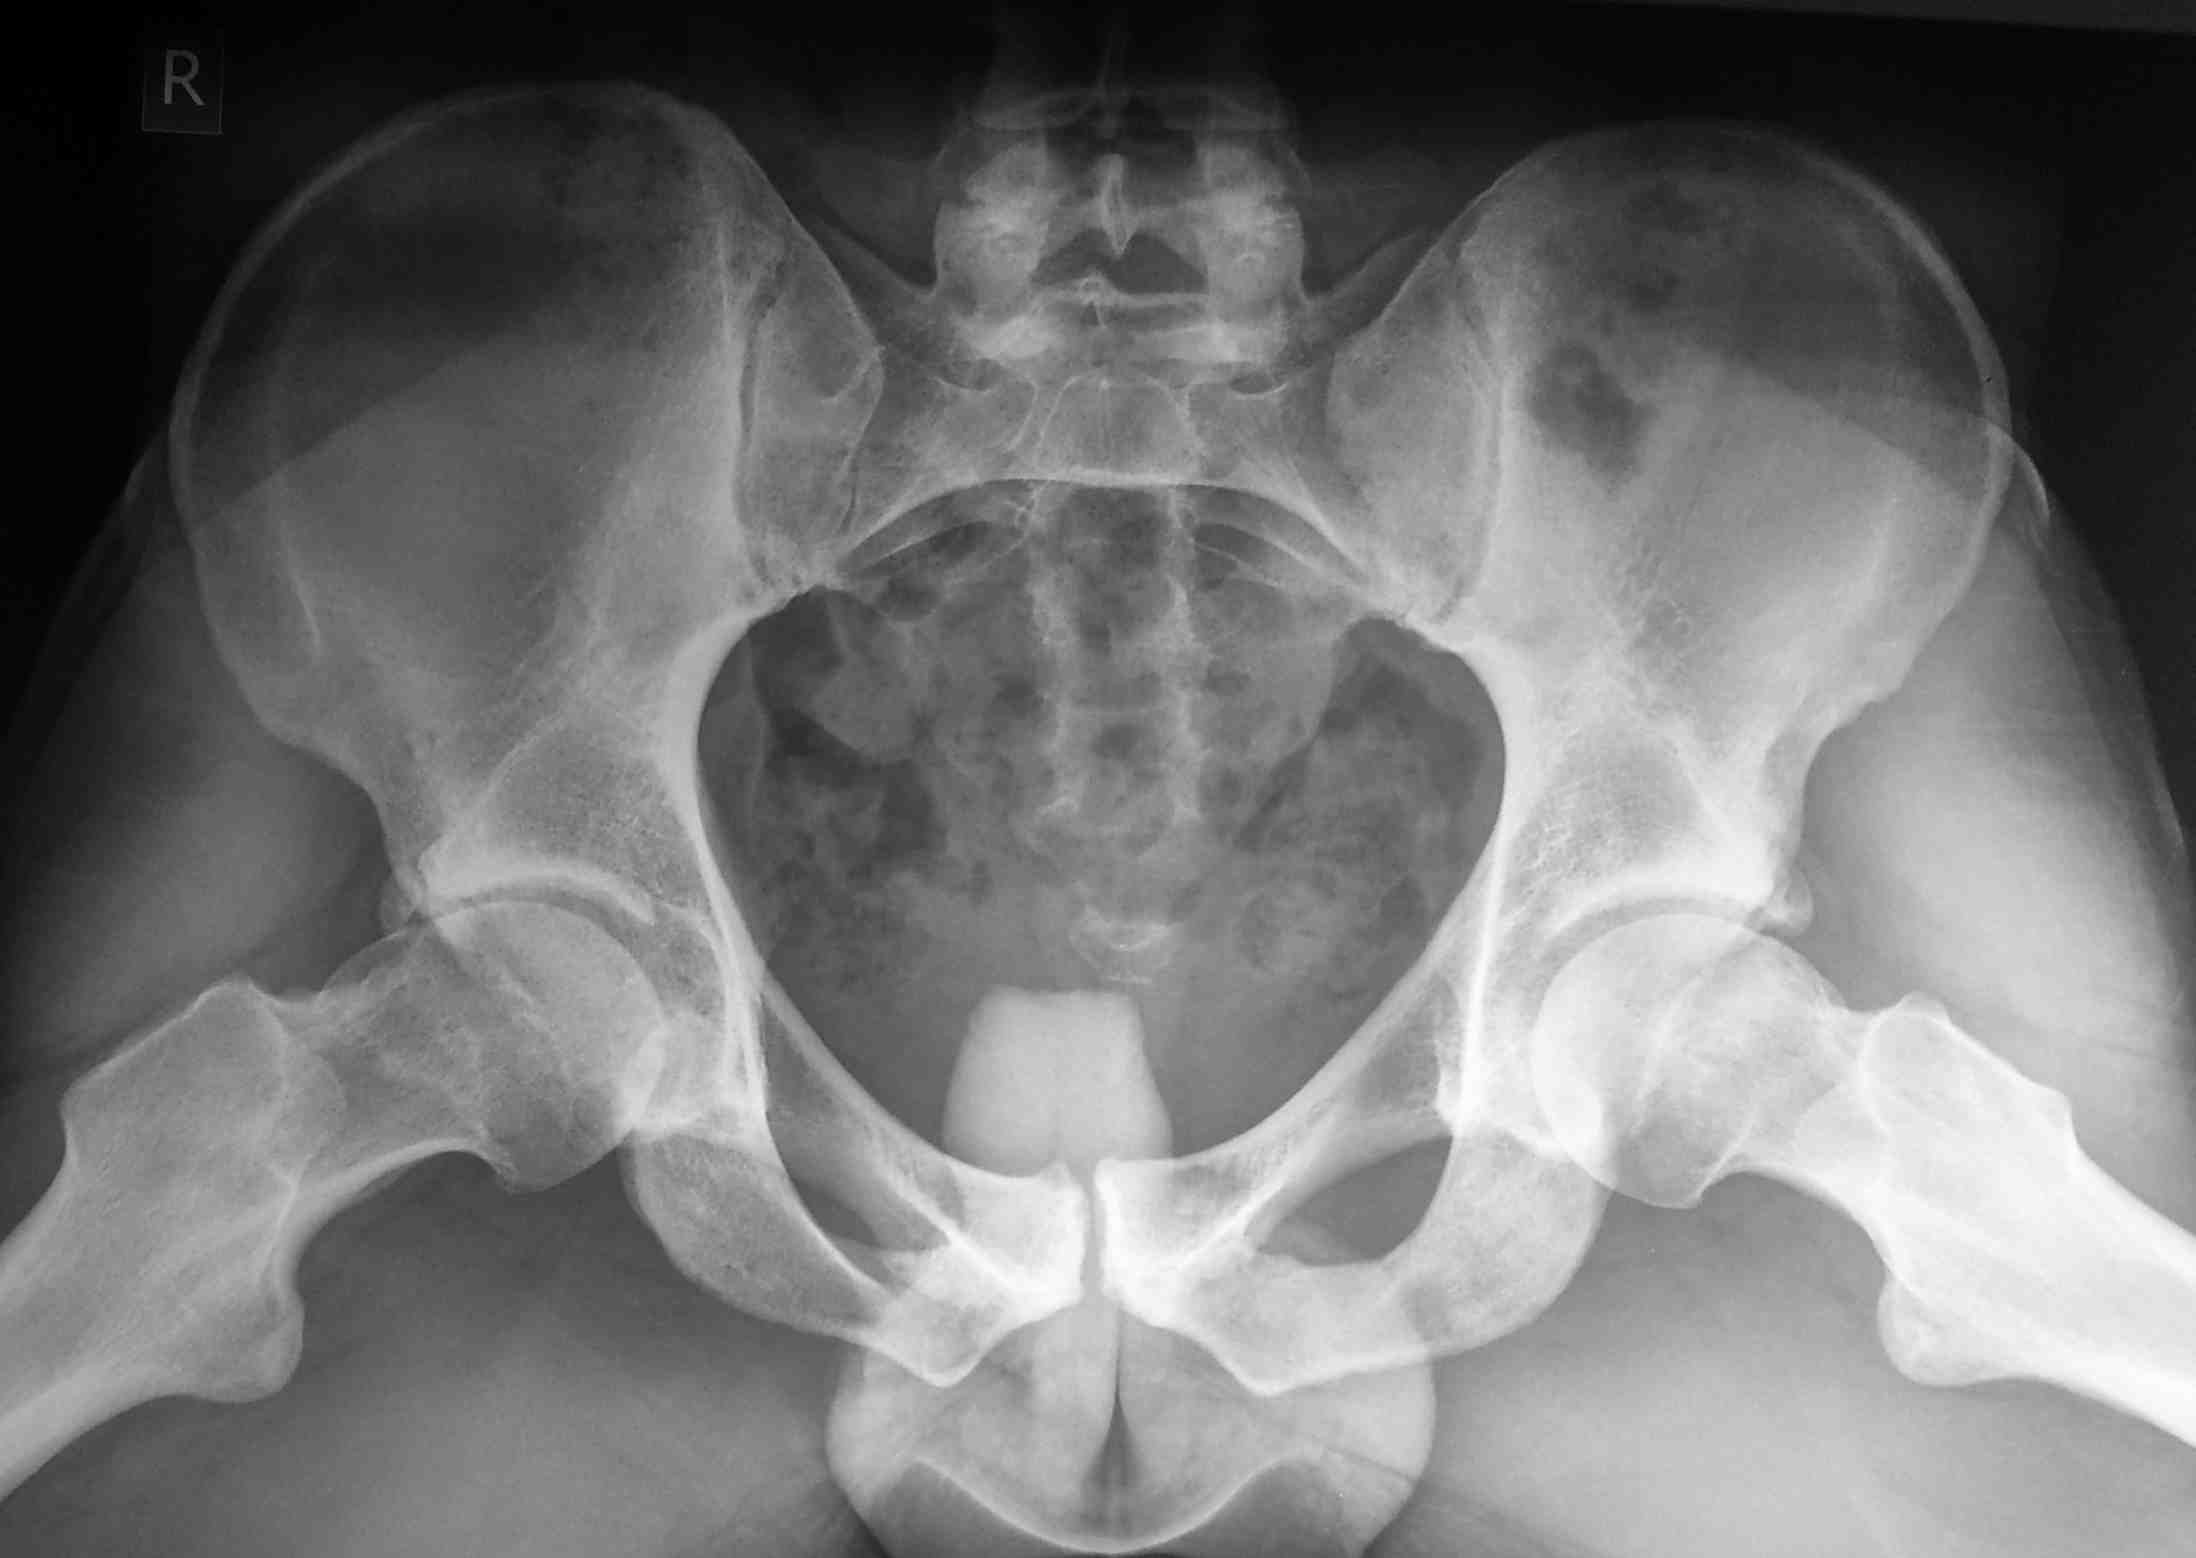

Обратился на консультацию молодой человек с жалобами на дискомфорт в

правом тазобедренном суставе.

объективно, имеется ограничение движений в правом т/б суставе, болевой

синдром минимальный. не курит, спортсмен. Вопросы: